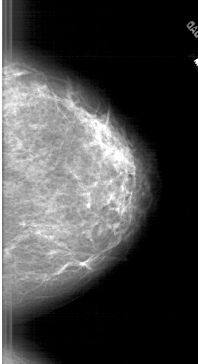

A_1905_1.LEFT_MLO

LEFT_MLO LINES 6406 PIXELS_PER_LINE 3121 BITS_PER_PIXEL 12 RESOLUTION 43.5 OVERLAY